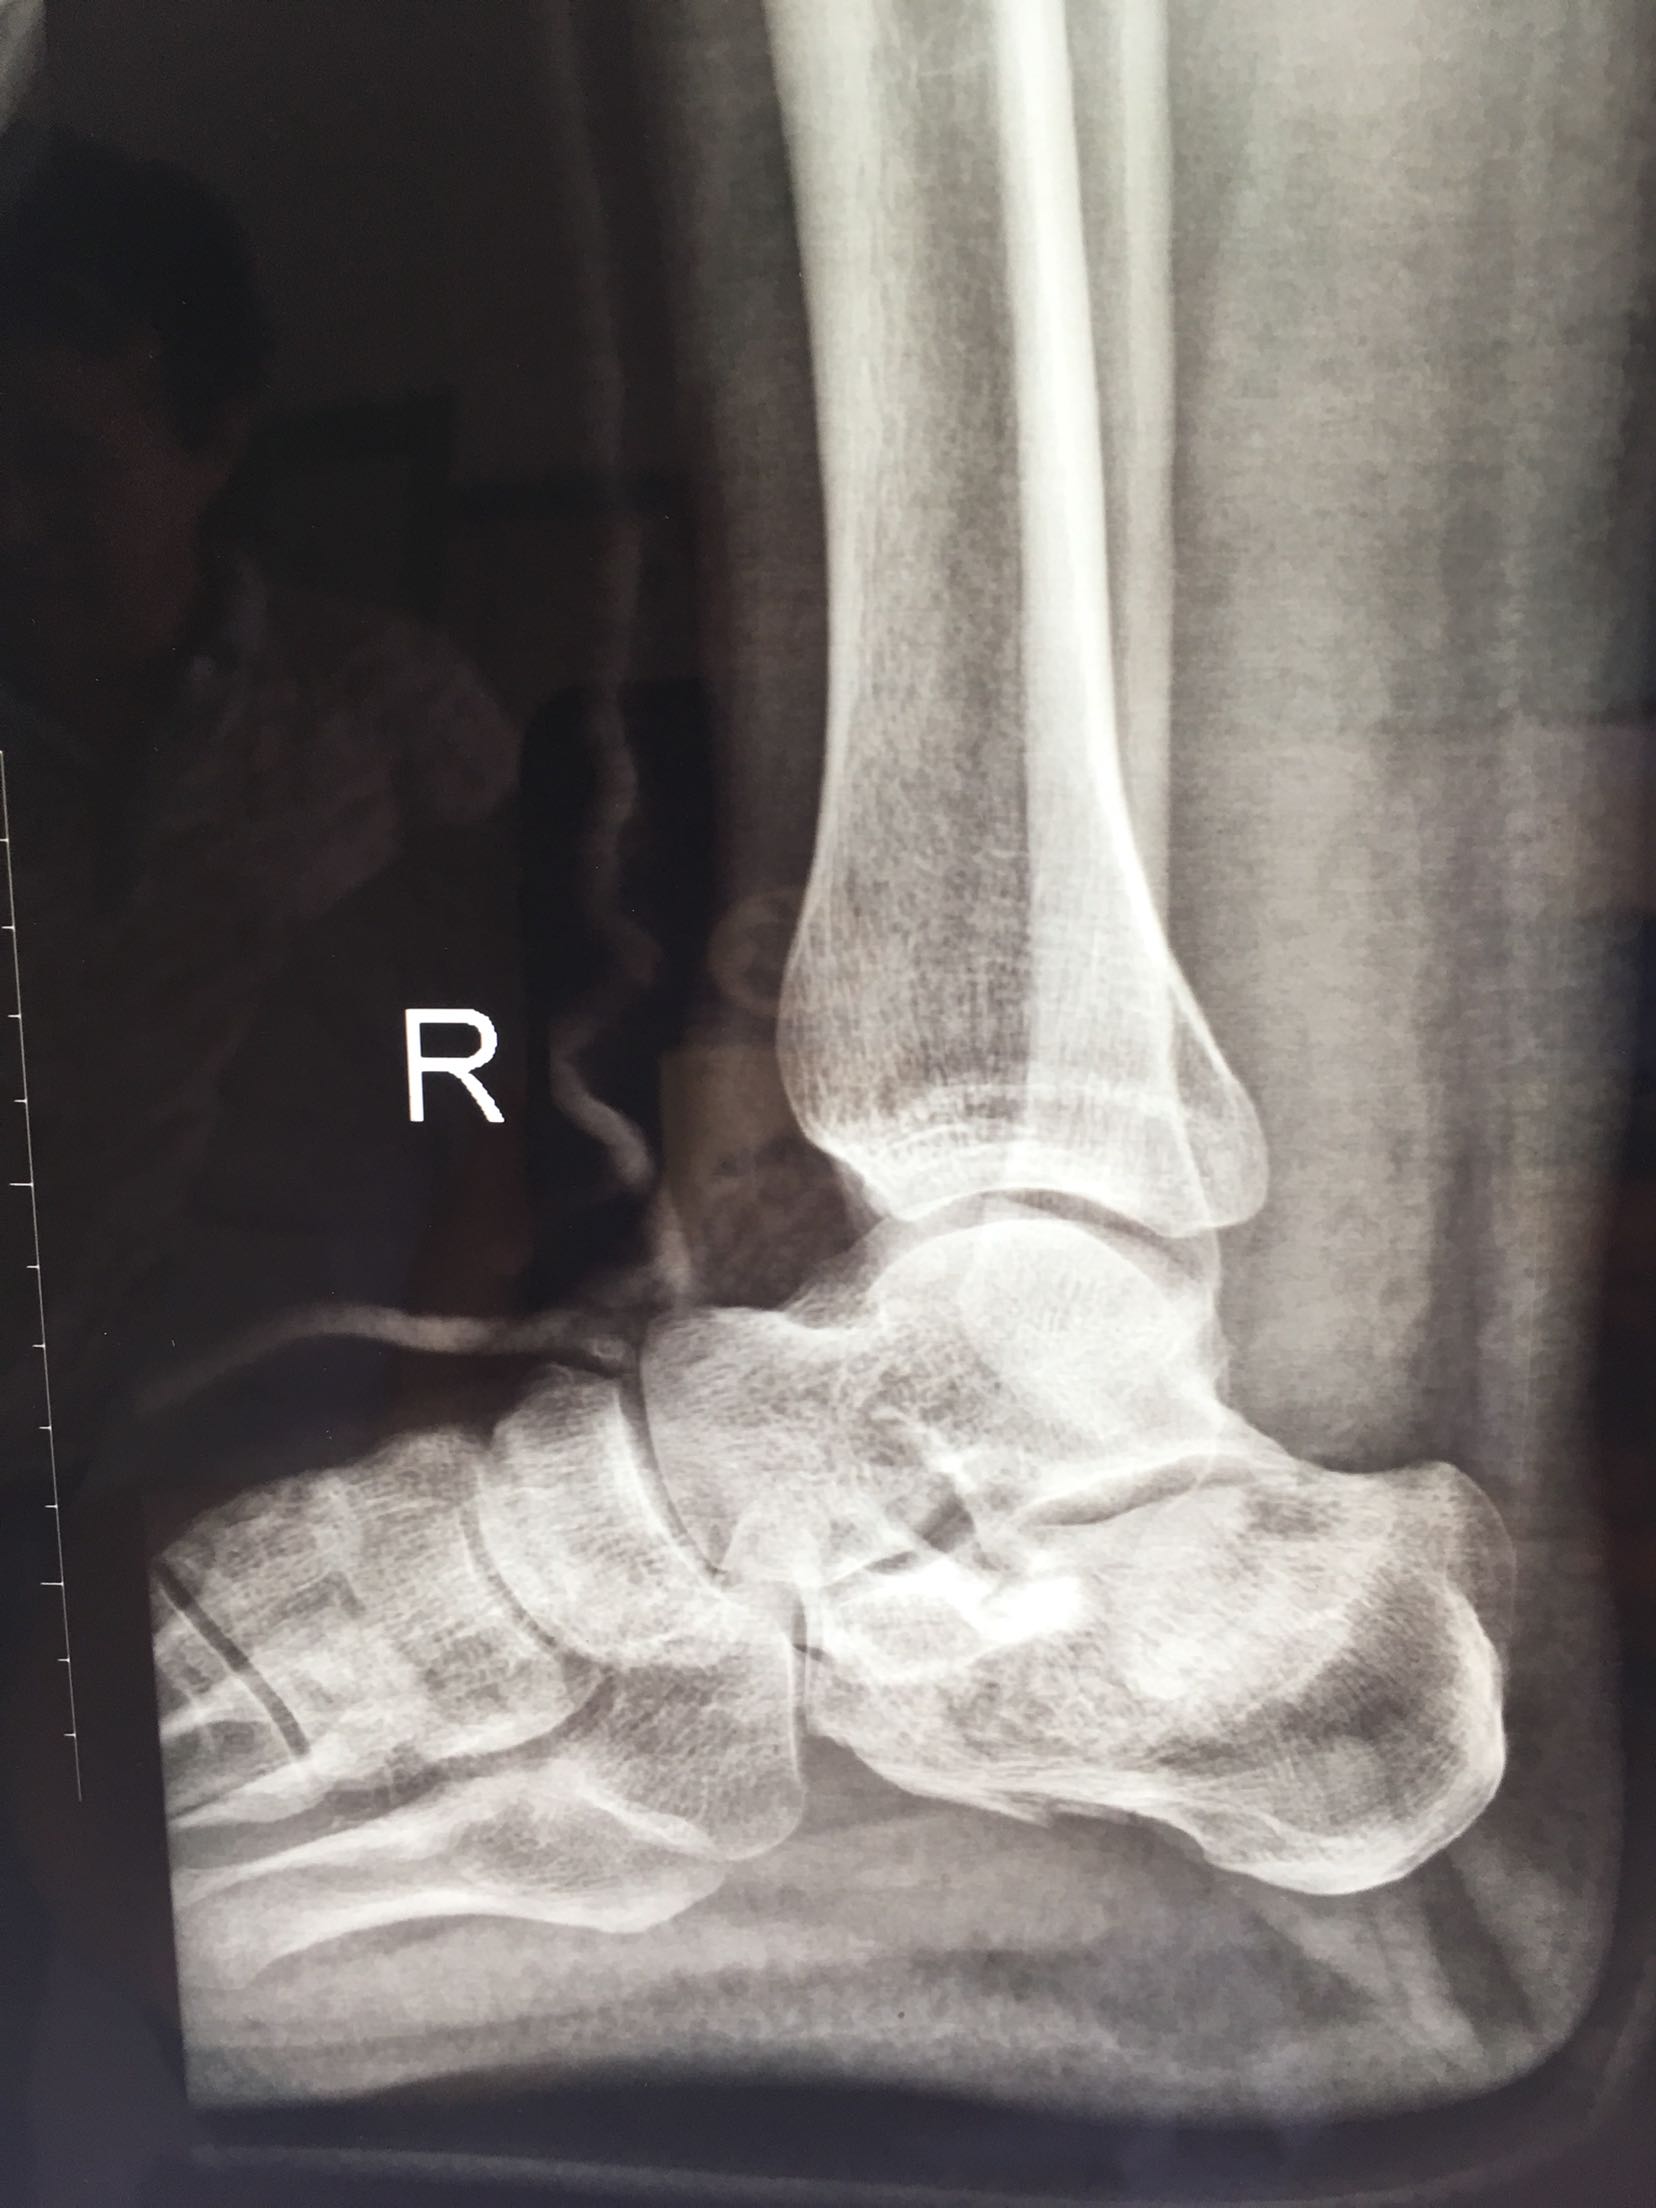

跟骨骨折